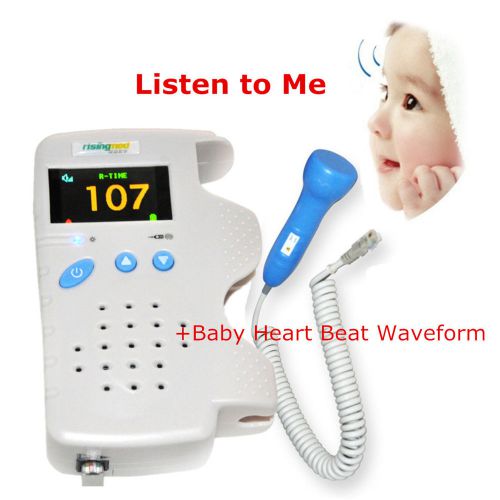

2015 Hot Sale Fetal Doppler 3MHz Color LCD Back Light & Heart Beat Waveform CE A

A+ Fetal Doppler 3MHz with LCD Display Baby heart monitor Prenatal Heart Monitor

Sonoline B Fetal Doppler Pocket

Angelsounds Fetal Prenatal Heart Rate Monitor Doppler 3MHz + Headset/earphone